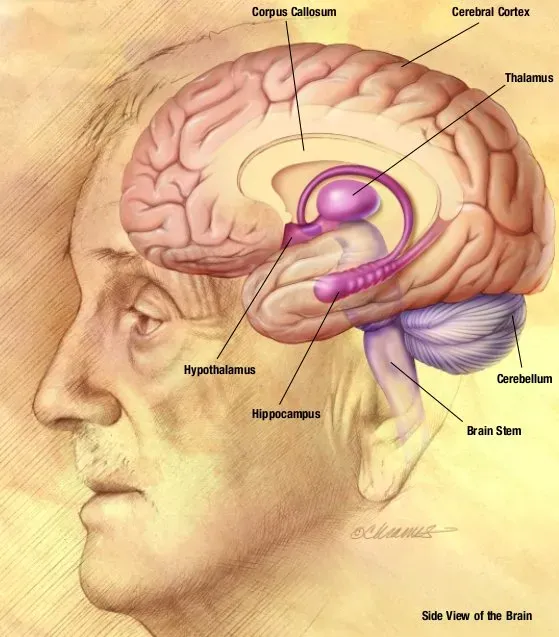

Your Brain Has a Built-In “Reality Signal” That Tells Real from Imagined

When you imagine an apple, your brain activity is not that different from when you actually see an apple. So how does your brain know the difference? It is a question that sounds almost philosophical, but science now has a concrete answer.

Scientists discovered a “reality signal” generated by a region of the brain called the fusiform gyrus, which is then evaluated by another region to determine whether something is real or imagined. Think of it like a built-in fact-checker running in the background of your mind at all times. The researchers think that dysfunction of this system could lead to hallucinations, in which people mistake something generated by the brain for something real. That finding alone could transform how we understand and treat conditions like schizophrenia.